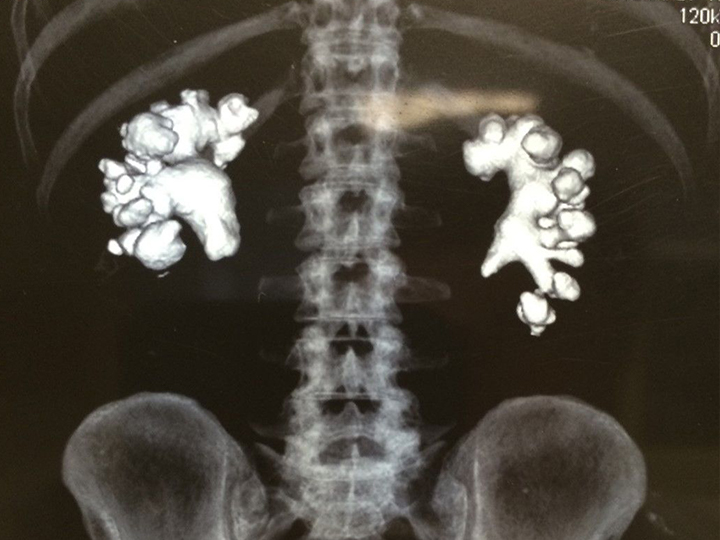

Камни, которые появляются в почках, различаются по составу и форме. Наиболее часто встречаются оксалатные, фосфатные, уратные и смешанные конкременты. Первые особенно опасны — они плотные, с «шипами» по краям, нередко травмируют слизистую и вызывают болевой синдром. Несмотря на это, современные методы диагностики и терапии позволяют успешно лечить мочекаменную болезнь как консервативно, так и хирургически.

По размеру камни могут варьироваться — от мелкого «песка» в мочевом пузыре до весьма внушительных экземпляров. Оперативное вмешательство требуется при крупных или коралловидных образованиях, особенно если их размер превышает 1 см или они нарушают отток мочи. Небольшие камни нередко удается вывести естественным путем, те, что побольше — раздробить в условиях стационара с помощью специальных технологий, например, литотрипсии, причем этот метод подходит и для фосфатов, и для оксалатов, и для уратов. (Подробнее о литотрипсии мы писали в одной из прошлых статей. – Прим. ред.) Однако при опасном расположении конкрементов в верхней, средней или нижней трети мочеточника требуется немедленное оперативное вмешательство.